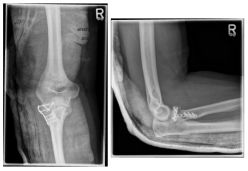

Ellenbogen2

Photo: A fracture with several framents

Ellenbogen3

Photo: The fracture on the left is after an operation with a plate and screws